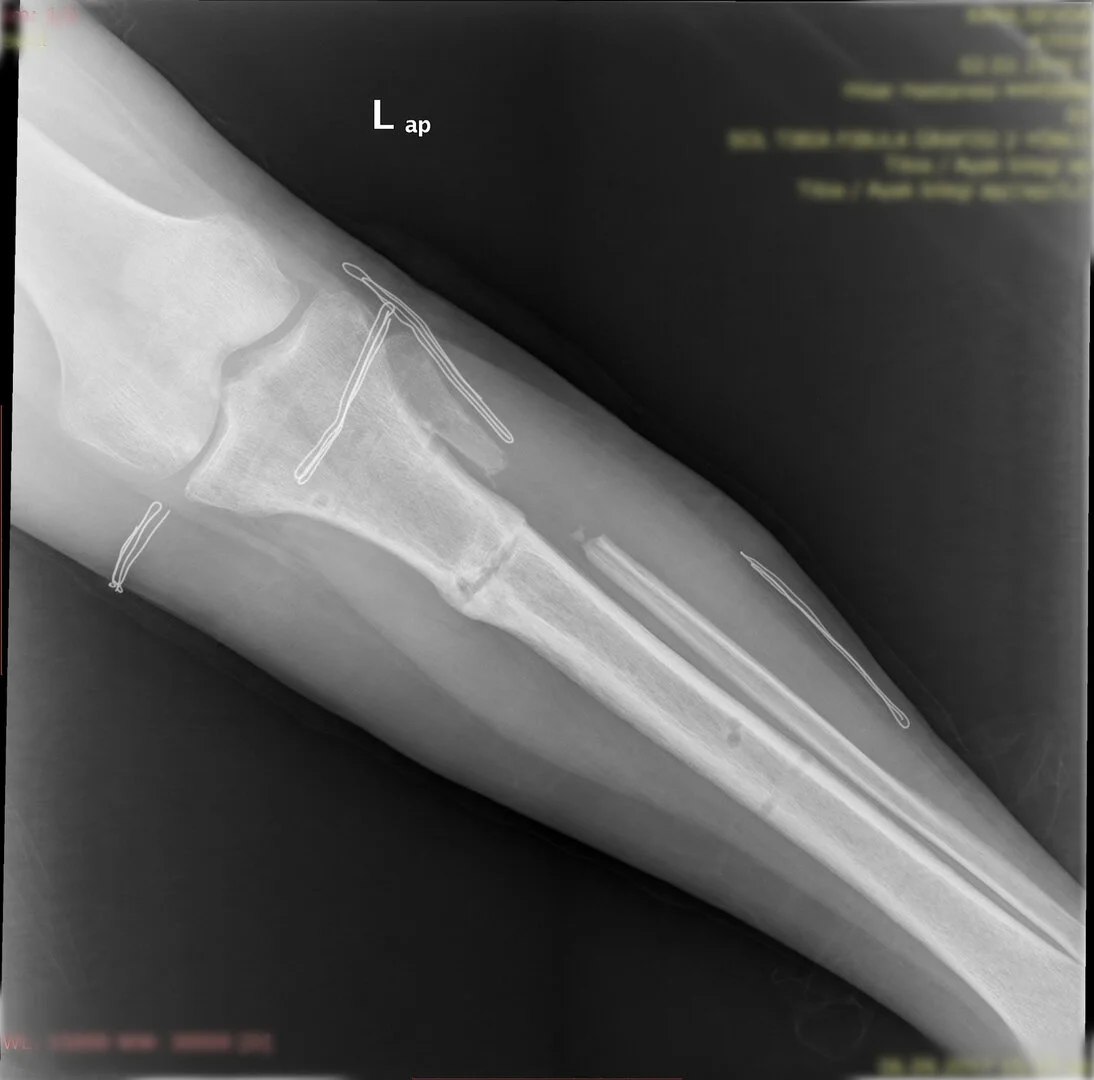

Diğer bir yöntem akut olarak düzeltme yöntemidir. Bu yöntemde kemiğe uygulanılan tespit yöntemi plak-vida kombinasyonu olabileceği gibi bir intramedüller çivi de olabilir.

Hangi tespit yöntemini kullanacağınıza deformitenin yeri ve miktarına göre karar vermek gereklidir.

Bu ameliyat öncesi bir deformite analizi yapılıp hangi kemikte, normalden ne kadar sapma olduğu tespit edilir. Daha sonra bu kemiğe yine ostetomi yapılarak bu anormal sapma düzeltilir.  Bu düzeltme plak-vida veya intramedüller çivi ile akut olarak düzeltilebileceği gibi bilgisayar destekli sirküler eksternal fiksatör ile tedrici olarak ta yapılabilir. Hangi yöntemin hangi hasta için uygun olacağına hasta özelinde karar veriyoruz, ne tür cerrahi tedavi olması gerektiğini danışabilirsiniz.

Görüntüleri büyütmek için üzerine tıklayınız.